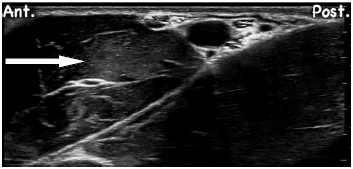

Observe a imagem relacionada ao bloqueio de plexo braquial ao nível axilar:

O músculo destacado pela seta é o: